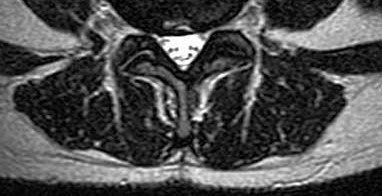

Question 13:

A 65-year-old male presents with neurogenic claudication. He reports pain radiating down both legs when walking, which is relieved by leaning forward on a shopping cart. MRI shows severe spinal stenosis at L4-L5. Which ligament thickens and contributes significantly to the dorsal compression of the thecal sac in this condition?

Correct Answer: Ligamentum flavum

Explanation:

In degenerative lumbar spinal stenosis, hypertrophy and buckling of the ligamentum flavum commonly cause dorsal compression of the thecal sac.